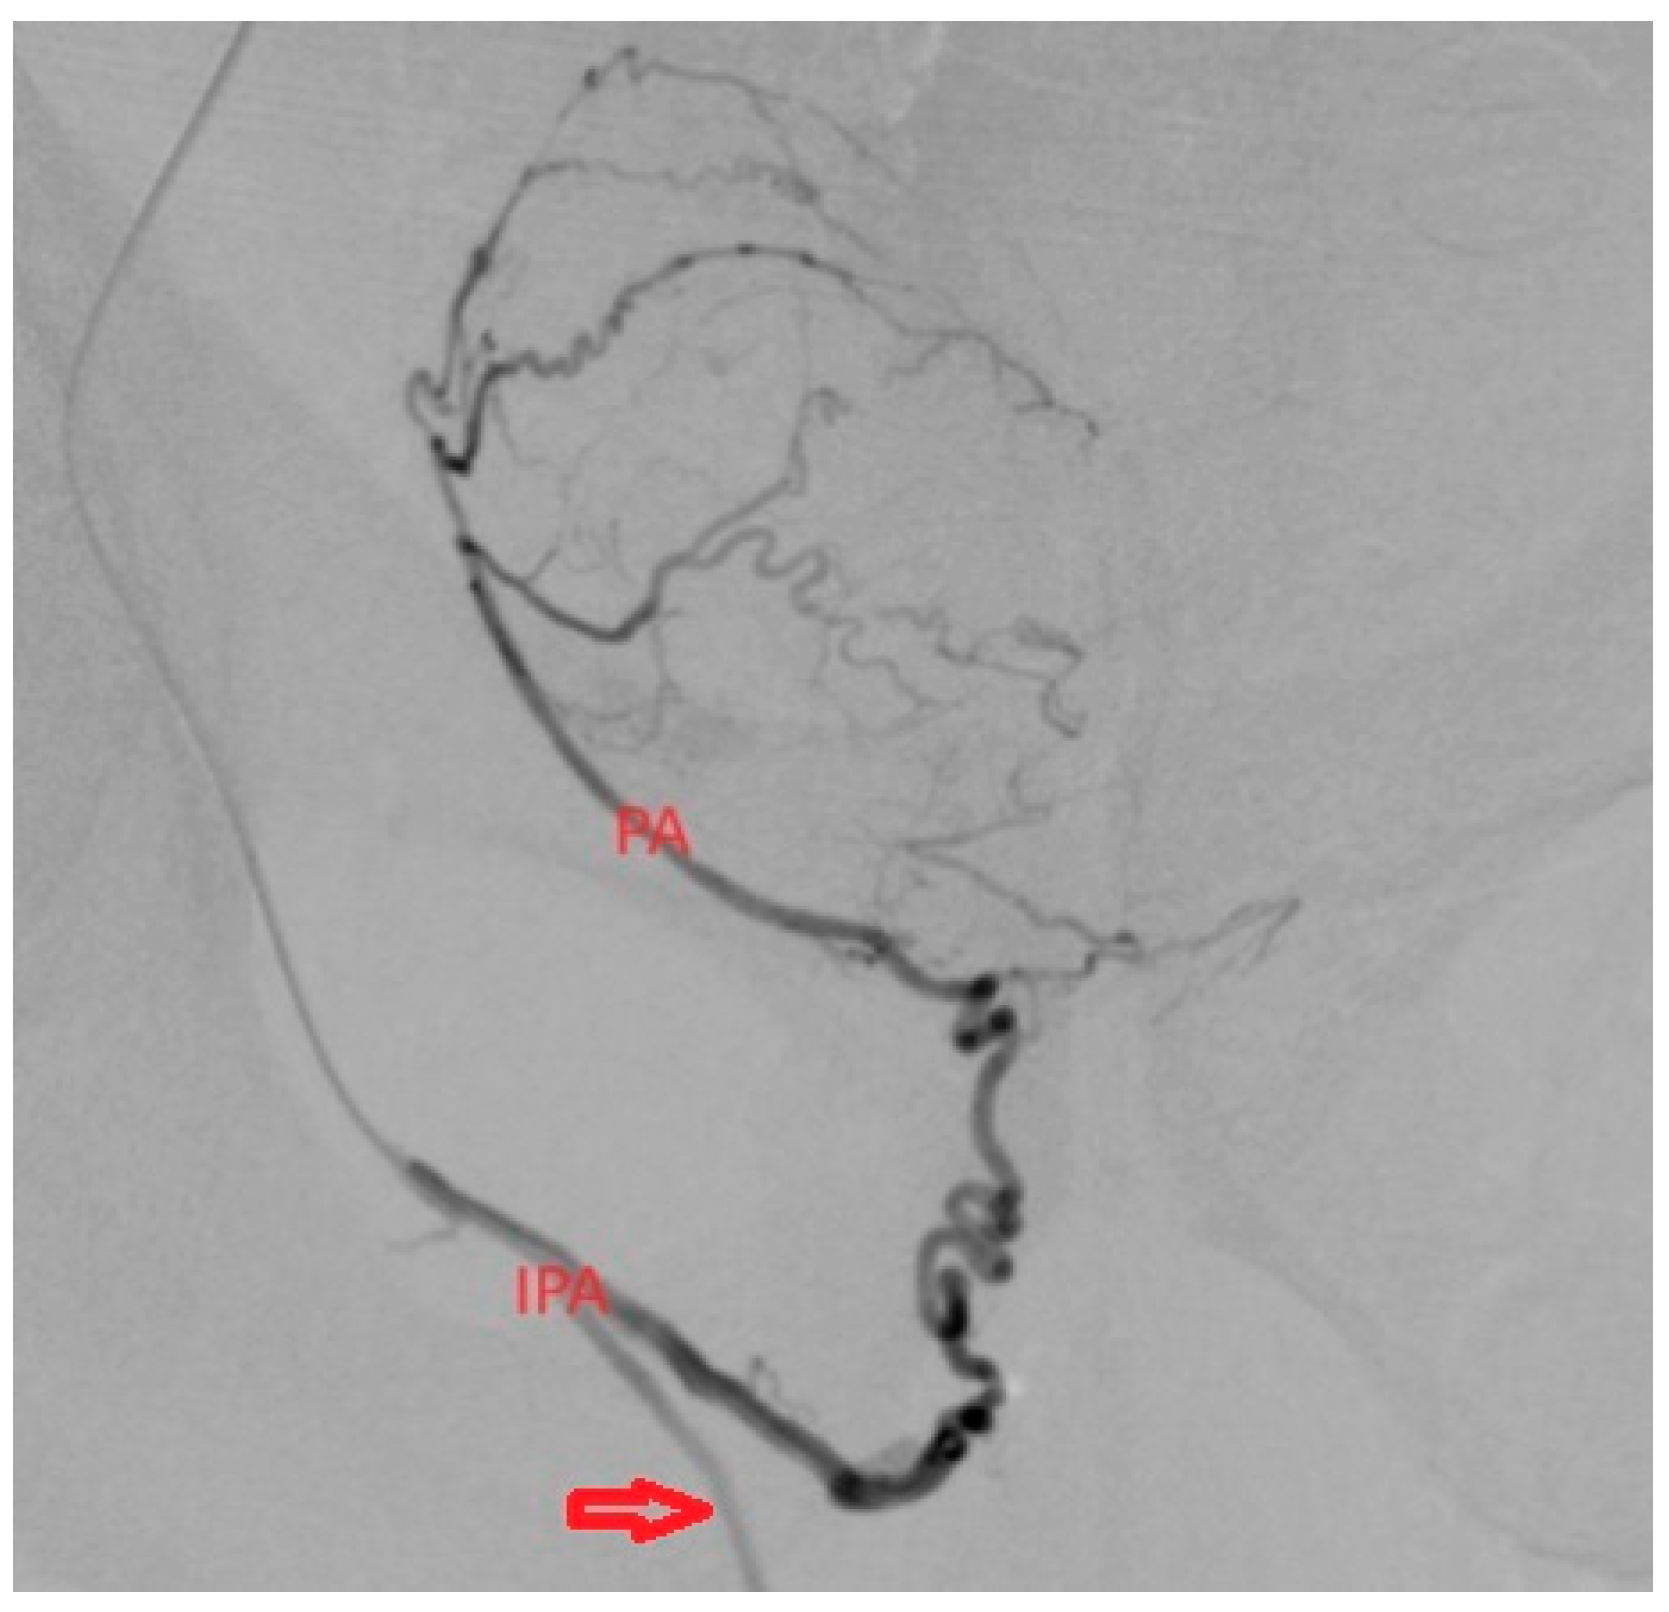

- Prostatic arteries realize the vascularization of the prostate, the anterior for the prostatic parenchyma and the posterior prostatic arteries for the prostatic capsule. Depending on the variability, we can frequently find a common trunk and a distal bifurcation near the prostate, but there are also cases of two PAs with different origins (Figure 1) [11].

3.1.1. PA with Origin from IPA

3.1.4. PA with Distal Origin from Internal Pudendal Artery